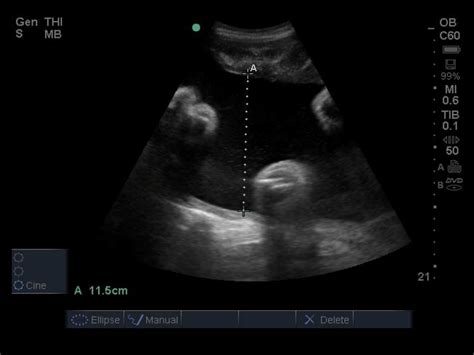

The Amniotic Fluid Index is a semi-quantitative estimation of the amount of amniotic fluid present in the uterus. During an ultrasound, the sonographer divides the uterus into four quadrants. They then measure the deepest pocket of amniotic fluid that is free of umbilical cord loops or fetal parts in each of these four quadrants. By adding the measurements of these four pockets together, they arrive at a total value, which is the Normal Amniotic Index. This method is preferred over measuring a single deepest pocket because it provides a more comprehensive overview of the fluid distribution throughout the uterine cavity.

The resulting number, measured in centimeters (cm), allows healthcare providers to determine if the fluid levels fall within the expected range for the current gestational age. If the level is too low, it is referred to as oligohydramnios; if it is too high, it is known as polyhydramnios. Both conditions warrant further investigation and closer monitoring by a maternal-fetal medicine specialist.